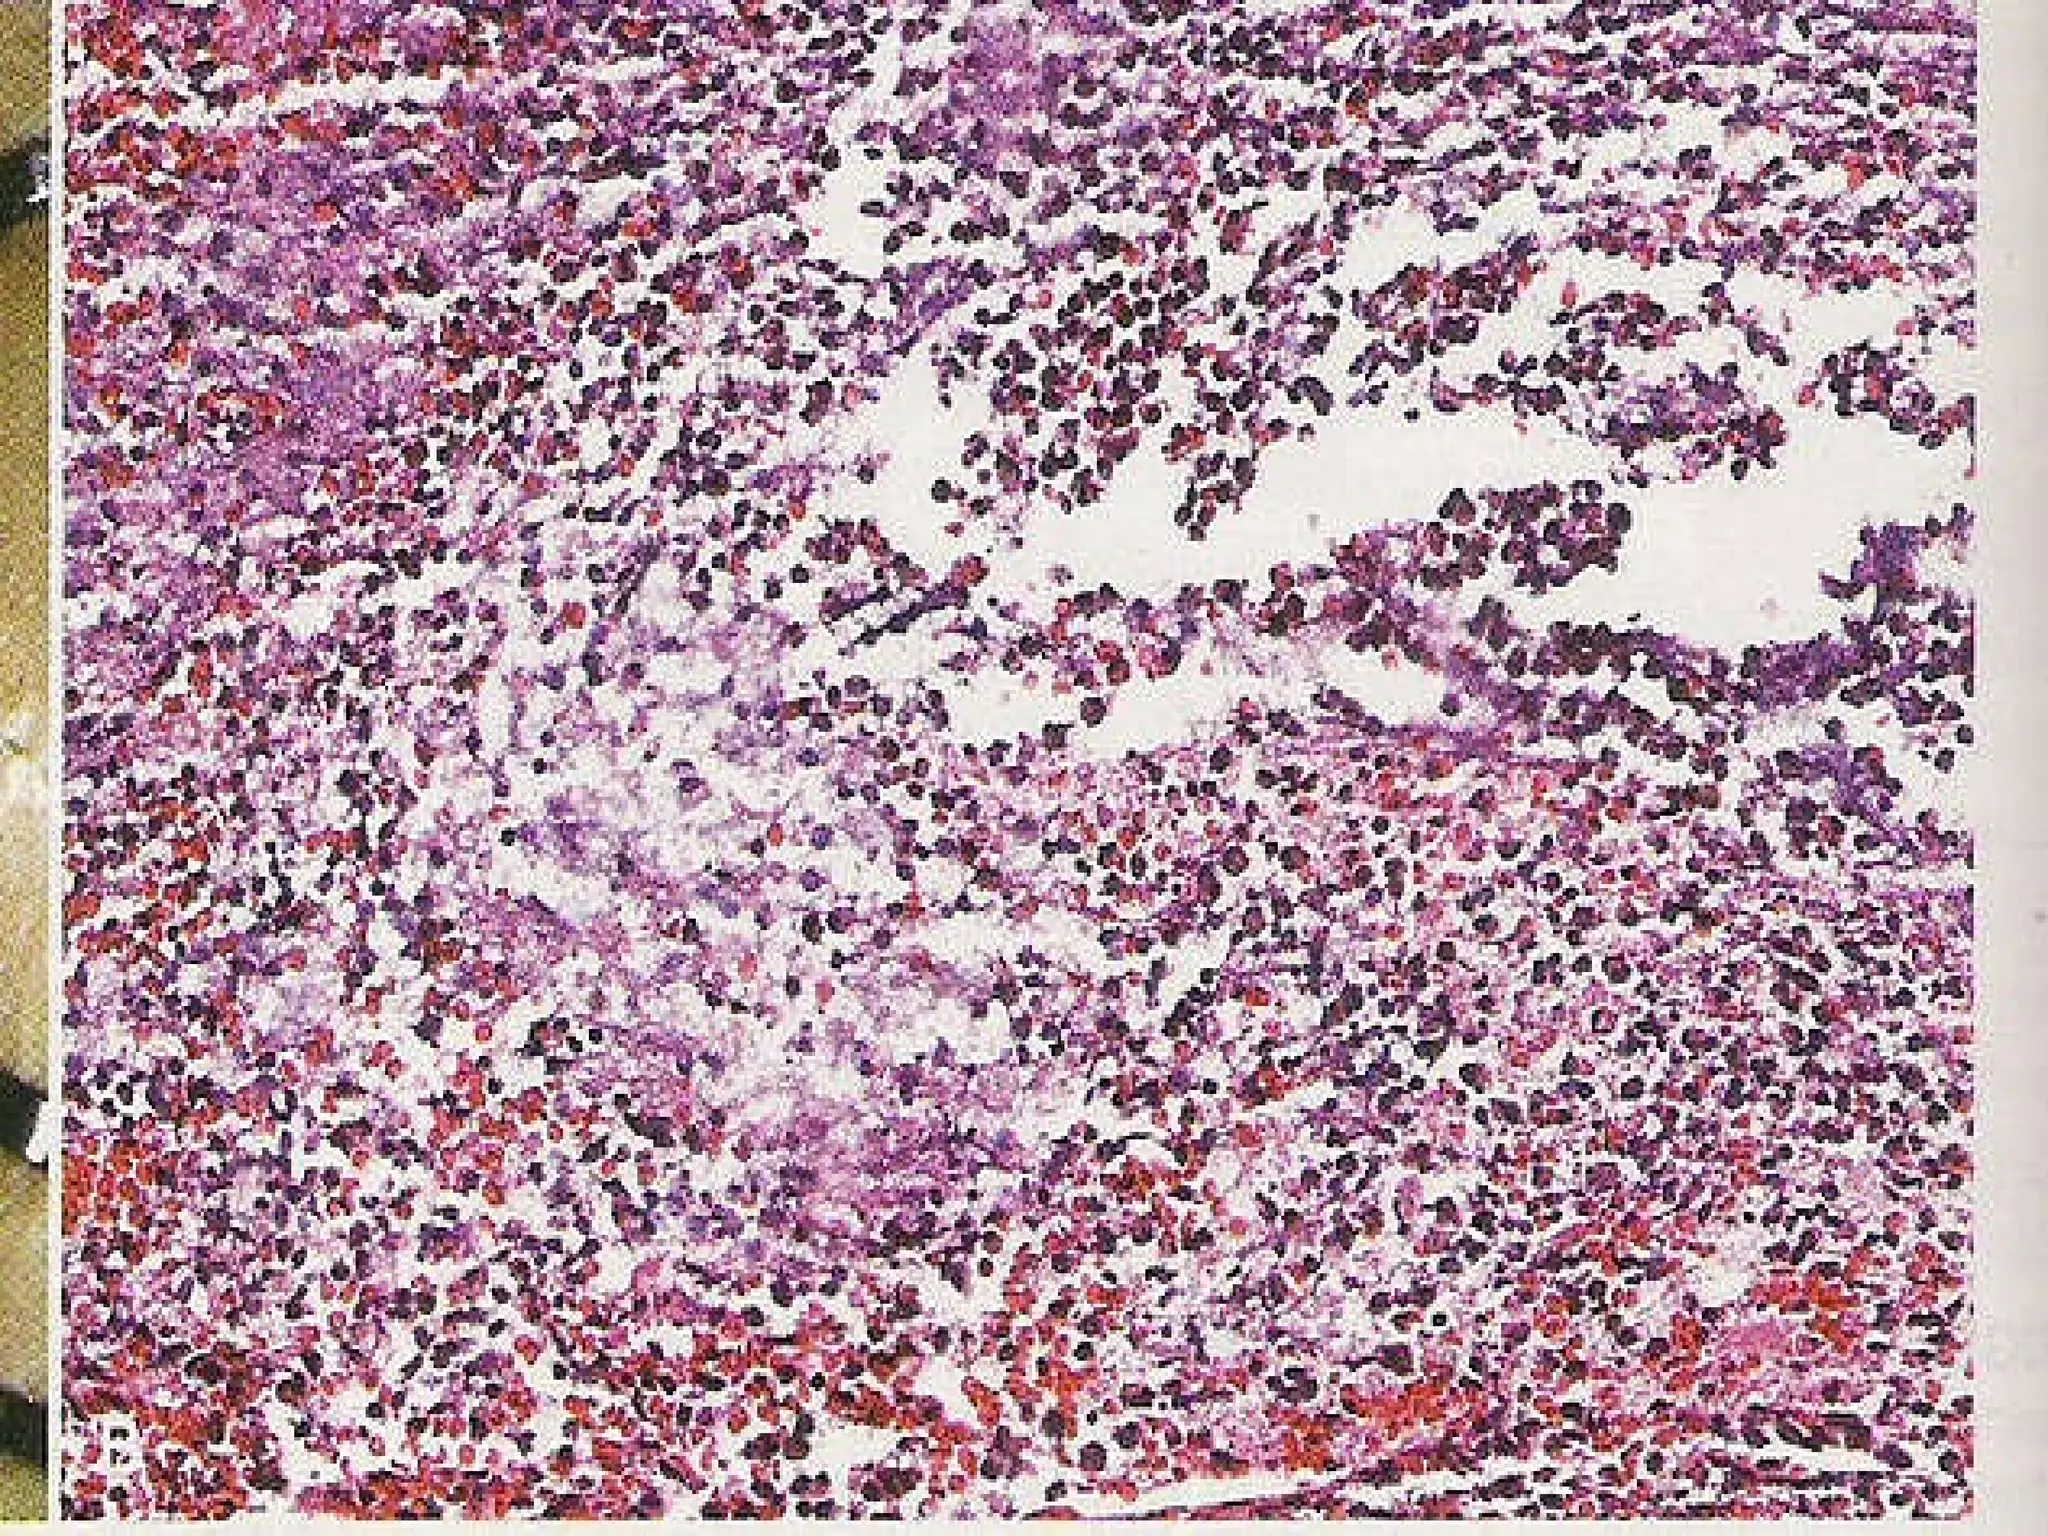

B. Emigration Adherent leukocytes > pseudopodia ↓ between 2 endothelial cells ↓ Basement memb.& perivascular sheath (damaged by collagenases & proteases on surface of migrating cells) First cells involved PMN – 1st 24 hrs ->  Monocytes/macrophages – next 24 hrs followed by lymphocytes & RBCs – follow by diapedesis.

Local sequelae of ac. Infln. Changes following ac. Infln. Depends on : 1. the amount of tissue damage  2. whether or not the causative agent remains. Some agents -> destruction of fixed tissues. If pt. survives,1.autolysis of the area> macrophages infiltrate-> healing by repair & regeneration 2.digestion of the area by lysosomal enzymes of PMN (pus cells) -> abscess. If no tissue death,- PMN -> mononuclears -> onset of demolition phase

Demolition phase Macrophages  (scavengers) engulf-fibrin,red cells ,pus cells, foreign materials, bacteria. - fuse to produce giant cells - act best when activated ( MAF identical to Interferon  gamma)↓ bacterial endotoxins phagocytose bacteria

End results(Contd.) 2. Suppuration Infl. reaction associated with necrosis ->  suppuration Necrotic material > softening > fluid pus in a cavity > abscess Pus – dead & dying leukocytes -- other components of infl. (oedema fluid,fibrin) --organisms  (many living – culture) -- tissue debris (nucleic acids & lipids) Epithelial surface involved > ulcer-- floor ->necrotic tissue,ac. Infl. exudate(slough)↓ gets detached– heals by repair &regeneration. Abscess > drained /not drained ↓ dense fibrous tissue,watery content absorbed,calcification.